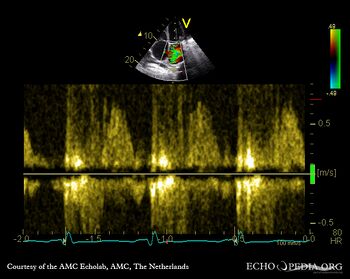

A4CH: moderate tricuspid regurgitation Coninuous-wave signal of moderate tricuspid regurgitation, increased systolic pulmonary artery pressure